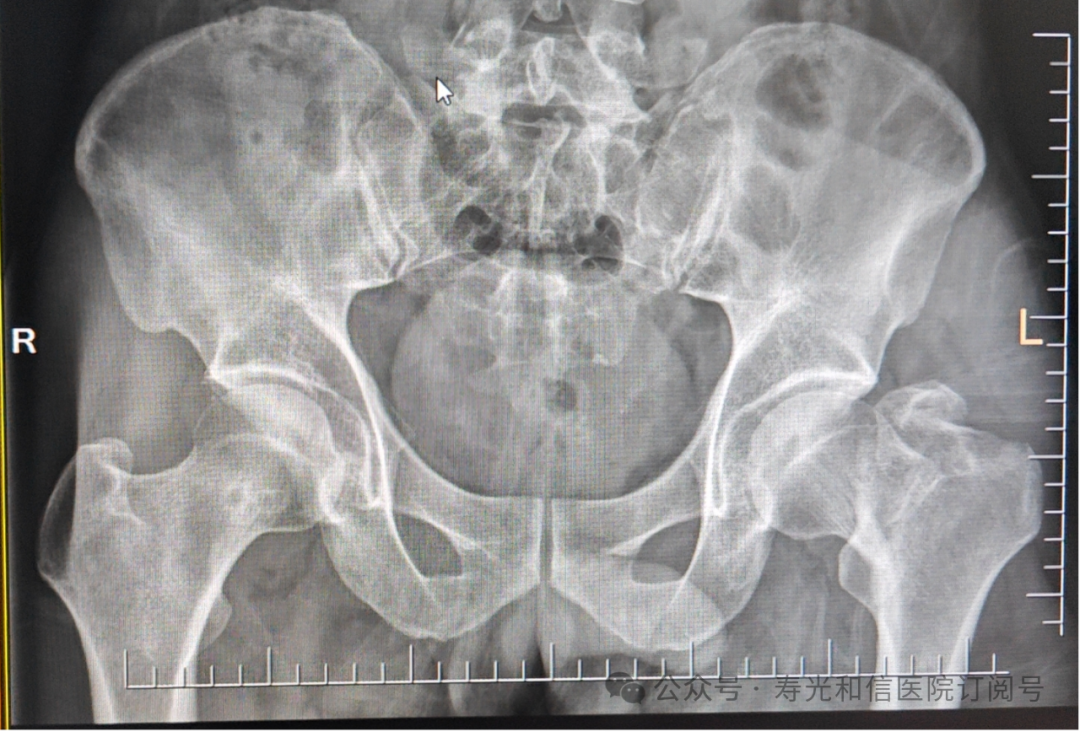

患者经120接诊,完善相关辅助检查后收入寿光和信医院骨外科。检查发现,患者右锁骨骨折、左股骨颈骨折、左大转子撕脱骨折、右膝关节前交叉韧带止点撕脱骨折、右膝关节外侧副韧带损伤、颅骨骨折及全身多处皮肤挫伤。因患者是外地来寿人员,家属短时间内不能赶过来,并且患者家庭经济条件较差,没有缴纳住院手术费的能力。但是股骨颈骨折后,股骨头坏死发生几率较高,手术越早进行,越有利于减少发生股骨头坏死的几率。骨外科主任李刚始终牢记救死扶伤的神圣职责,本着为病人负责的原则,坚定地选择先行为患者实行手术治疗。

与患者本人充分沟通后,李刚主任率领骨外科团队,经过充分的术前讨论及术前准备,于2024年9月1日为患者在全身麻醉下实施了4个半小时的内固定手术治疗。“时间就是生命”,手术过程中,全体参与人员密切观察病情变化,敏锐发现早期异常指标,争分夺秒,一丝不苟地做好各项抢救救治工作,做到瞬间判断、正确评估、果断处理,赢得了抢救患者的“黄金时机”,确保了手术的顺利完成。

在为其进行股骨颈骨折治疗时,手术团队为其采取了股骨颈动力交叉钉系统,这是一种新型股骨颈内固定系统,属微创植入,较从前的技术具有手术时间短、创伤小、力学稳定、滑动加压等优点。同时,患者恢复快,可早期离床、不负重下活动,缩短住院时间及康复时间,有效降低患者股骨颈骨折不愈合发生率,降低长期卧床合并症和死亡率。